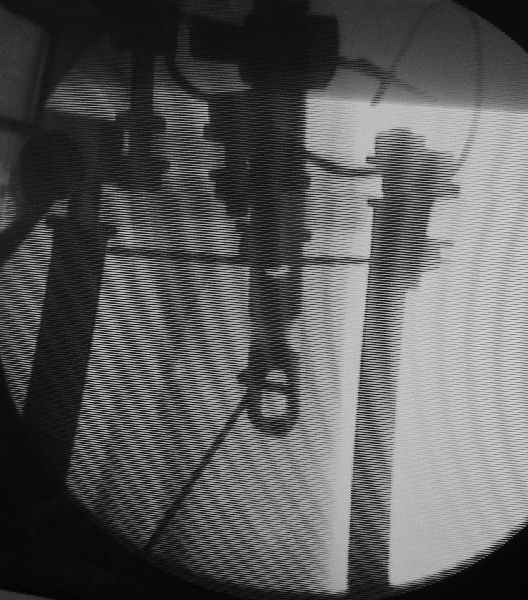

Вот картинка с ЭОП - гвоздь проходит центральный отломок, видно, как спица не дает ему отклониться к задней стенке канала.